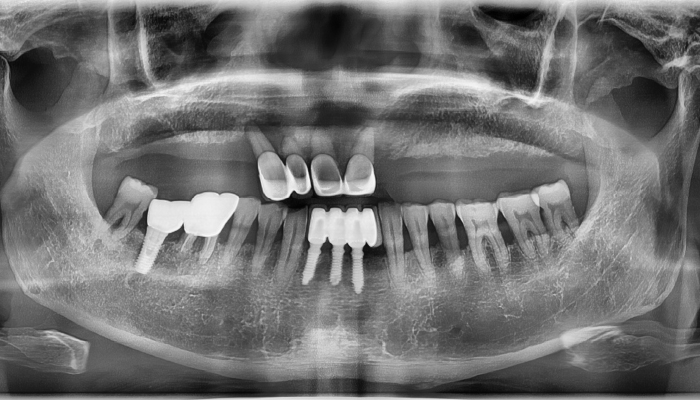

내비게이션 임플란트 수술

김OO님 전후사진 / 치료 기간 : 8주 / 식립갯수 : 전악

내비게이션 임플란트 수술

고OO님 전후사진 / 치료 기간 : 12주 / 식립갯수 : 11개

내비게이션 임플란트 수술

남OO님 전후사진 / 치료 기간 : 8주 / 식립갯수 : 10개

내비게이션 임플란트 수술

김OO님 전후사진 / 치료 기간 : 6주 / 식립갯수 : 3개